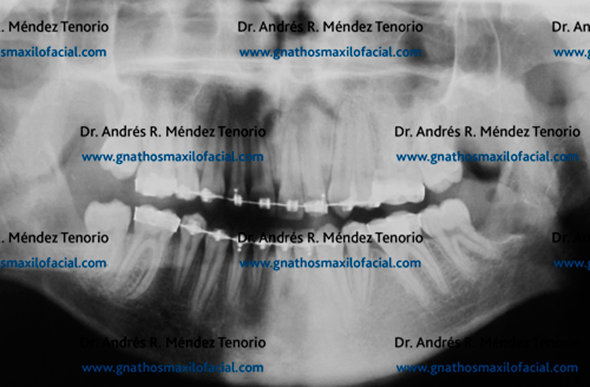

|

| Tras la extracción de estas piezas dentales y la rehabilitación dental, la higiene y la comodidad del paciente se incrementan con una dentición hasta el 2º molar en los cuatro cuadrantes de los maxilares |